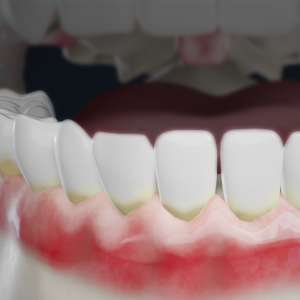

FAQ What is gum recession? Gum recession occurs when gum tissue pulls away from the tooth, making teeth appear longer